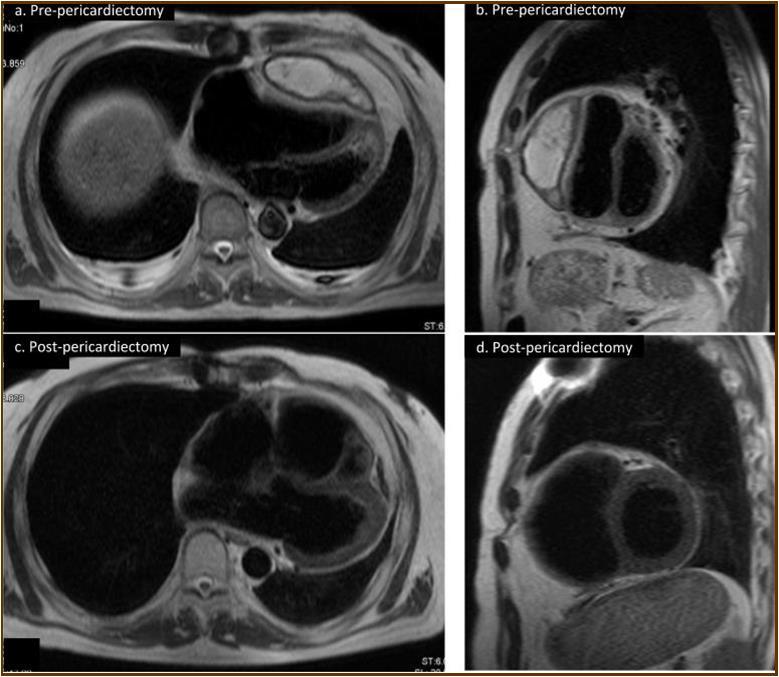

Figure 2.Magnetic resonance imaging findings. A thick cystic-like capsule which was tightly adhered to the right ventricle was seen (a. transverse view; b. sagittal view). A cystic-like capsule was removed after pericardiectomy (c. transverse view; d. sagittal view).

At the age of 52 years, the patient was admitted to our institution for both evaluation of heart failure and regular right heart catheterization including EMB. With respect to allograft rejection, ACR was again detected on regular EMB, and the immunosuppressive regimens were strengthened. Further echocardiographic investigations were conducted to explore the implications of findings indicative of constrictive physiology with thickened pericardium. Respiratory variation in both mitral and tricuspid inflow velocities was seen, but these findings did not meet the complete criteria for CP diagnosis (Figure 1c-e). Magnetic resonance imaging of the heart revealed seroma and a thick cystic-like capsule tightly adhered to the right ventricle (Figure 2a, b). Right heart catheterization revealed elevation of right atrial pressure with severely reduced cardiac index (Figure 3a). The classic dip-and-plateau pattern of right ventricular diastolic pressure and equalization of right atrial pressure and right ventricular diastolic pressure were also observed (Figure 3b). Based on these results, effusive CP or cardiac tamponade-like hemodynamics were strongly suspected, although the etiology remained unknown. Therefore, at 3 years post-HTx, the patient initially underwent removal of the seroma through exploratory lateral thoracotomy to elucidate the etiology of the disease. Yellowish fluid was found and the fluid was completely aspirated. Immunosuppressive regimens including everolimus, which may interfere wound healing, were temporarily converted to standard three-drug regimens. Removal of the seroma via lateral thoracotomy did not lead to improvement in symptoms or hemodynamics. Pathological analysis revealed fibrin and seroma, but no malignant cells or infection. Since the initial procedure did not have any effect on the patient’s symptom, pericardiectomy through median sternotomy was performed at two months after the initial procedure. Intraoperative findings indicated a thickened pericardium and effusion in front of the right ventricle. At first, after sternotomy and adhesiotomy, the tissue in front of the right ventricle, which appeared to be thickened parietal pericardium, was completely resected and the effusion fluid was removed. However, high central venous pressure (20 mmHg) persisted, resulting in a displacement of the left ventricle by the right ventricle. Therefore, additional tissue from the front of the right ventricle was excised, corresponding to diffusely thickened visceral pericardium and epicardium. After the procedure, central venous pressure decreased from 20 to 10 mmHg, and displacement of left ventricle resolved. Pathological analysis of the resected tissues demonstrated chronic fibrosis and chronic inflammation with plasma cells, but no infectious etiology was identified (Figure 4 a, b). After the pericardiectomy, hemodynamics (Figure 3a, c) and symptoms improved, and the patient is currently experiencing a favorable clinical course without complications.